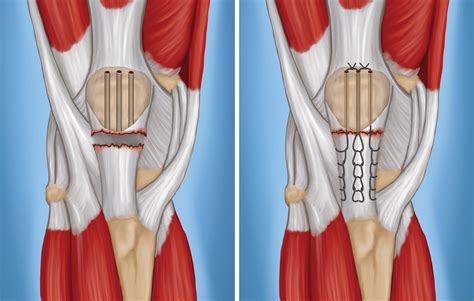

Surgical repair is often recommended for complete tears or when non-surgical treatment is ineffective. The procedure involves:

• Surgical Repair: Reattaching the torn tendon to the patella or tibia using sutures or anchors.

• Grafting: In some cases, a graft from another tendon or synthetic material may be used to reinforce the repair.